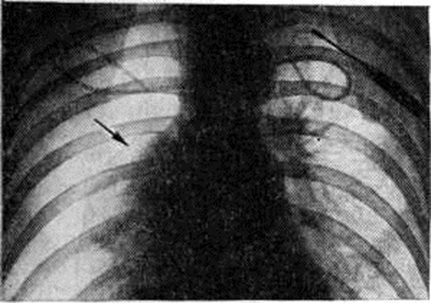

При клапанном (вентильном) Пневмоторакс спавшееся лёгкое не меняет своих размеров и конфигурации при дыхании, степень спадения лёгкого максимальная, средостение резко смещено в здоровую сторону, а на вдохе несколько перемещается в сторону поражения. Длительное нагнетание воздуха в плевральную полость при клапанном Пневмоторакс приводит к образованию напряжённого Пневмоторакс; при этом обнаруживается резкое смещение средостения в противоположную половину грудной клетки, диафрагма расположена низко, уплощена. Нередко определяется газ в мягких тканях грудной стенки. При тотальном Пневмоторакс газ занимает всю плевральную полость, тень средостения смещается в здоровую сторону (рисунок 2), купол диафрагмы опускается книзу.

Рис. 2.

Рентгенограмма грудной клетки при тотальном левостороннем пневмотораксе: прозрачность левой половины грудной клетки повышена, лёгочный рисунок не определяется, видна тень спавшегося лёгкого (указана стрелкой).